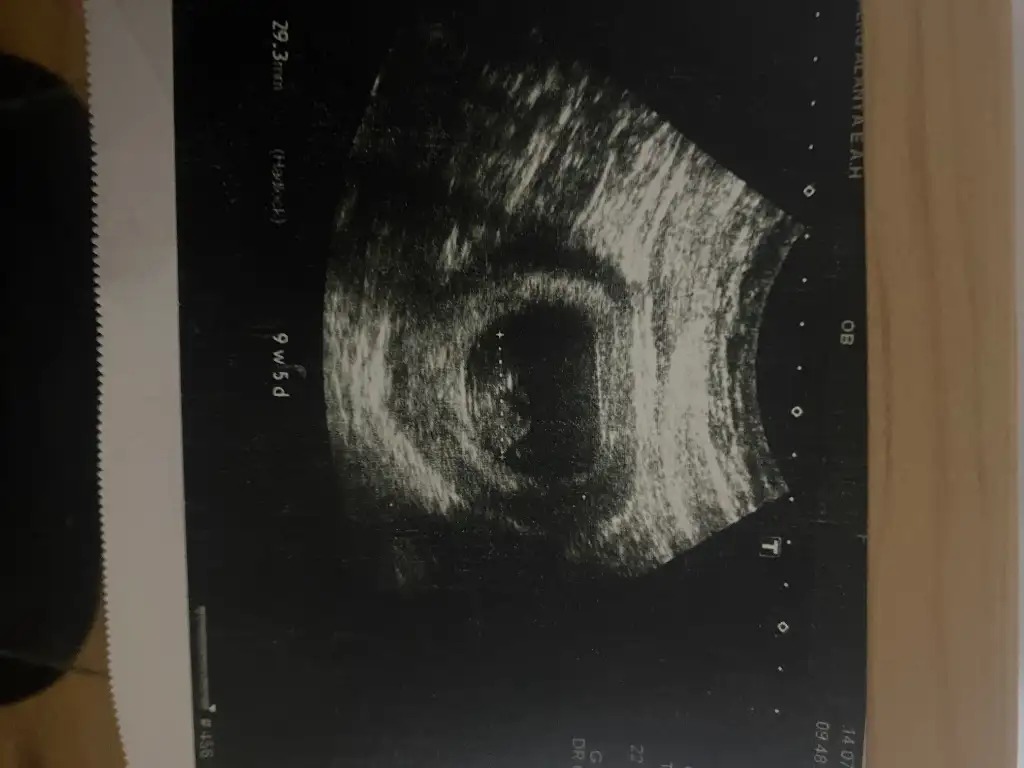

Ay benim için erken haftaya tekrar gideceğiz ama tahmin var mı atayım

Eklentiler

• IMG_6085.webp

45,8 KB · Görüntüleme: 22

• IMG_6090.webp

23,4 KB · Görüntüleme: 24